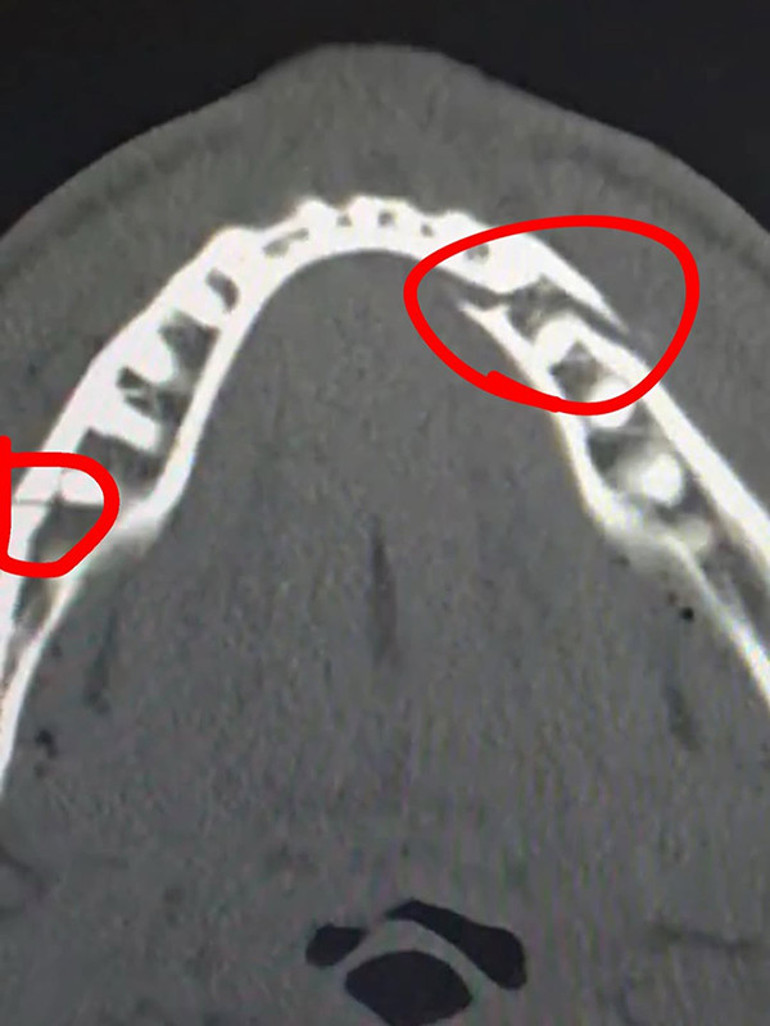

Jake Paul "Kendimi iyi hissediyorum, çok eğlenceliydi. Çenem kırıldı. Bir gün geri döneceğim ve dünya şampiyonluğu kemerini alacağım." açıklamasında bulunmuştu.

"Ameliyat iyi geçti, tüm sevginiz ve desteğiniz için teşekkürler. Her iki tarafa 2 titanyum plaka takıldı. Bazı dişler çekildi. 7 gün boyunca sadece sıvı gıdalar tüketmem gerekiyor."

Paul, çenesindeki çift kırığı gösteren röntgen görüntüsünü de sosyal medya hesabından paylaştı: